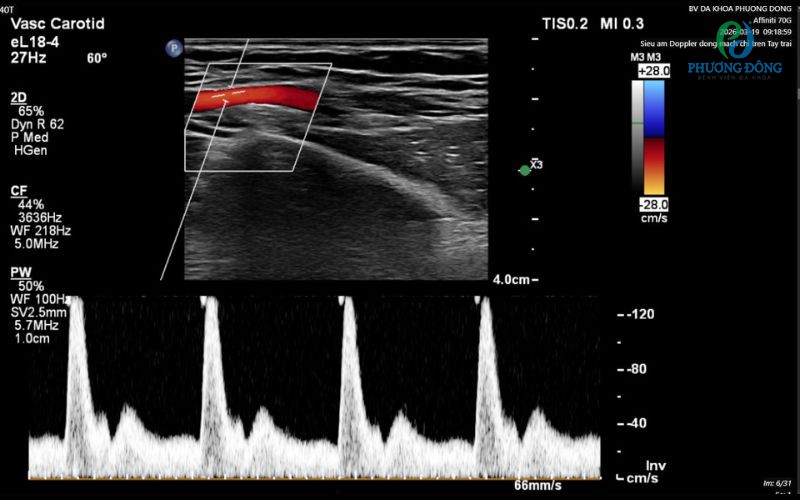

Siêu âm Doppler là kỹ thuật siêu âm màu kết hợp Doppler sử dụng sóng âm cao tần (2–10 MHz) để:

• Đo chính xác vận tốc dòng máu (peak systolic velocity – PSV, end-diastolic velocity – EDV), chỉ số kháng lực (RI), chỉ số xung (PI).

Nói dễ hiểu: giống như “chụp video HD + đo tốc độ xe” của dòng máu trong mạch bạn. Máy sẽ hiển thị màu đỏ/xanh (hướng chảy), đồ thị sóng (spectral Doppler) và hình ảnh 2D siêu rõ nét. Không dùng tia X, không chất tương phản, an toàn tuyệt đối cho mọi đối tượng kể cả trẻ em và bà bầu.

• Phân tích: Máy hiện ngay hình ảnh màu, đồ thị sóng Doppler, chỉ số chính xác. Bác sĩ chuyên khoa Chẩn đoán hình ảnh giải thích ngay kết quả, in màu hoặc lưu file điện tử.